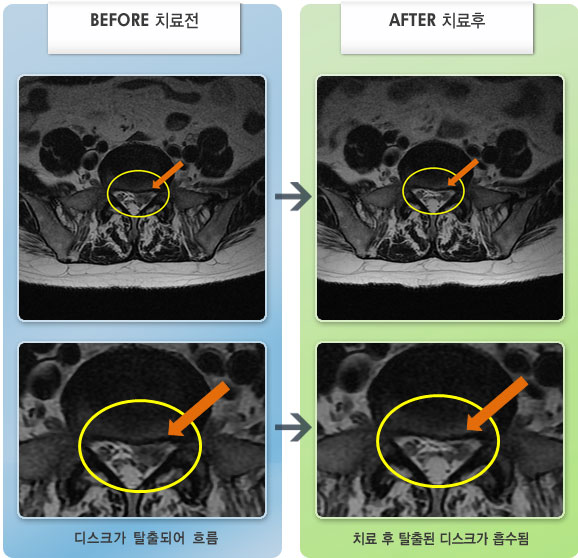

허리디스크

보라매 · 왕오호 원장

좌측 허리 통증과 좌측 다리 저림

촬영시기

2017.08.26 ~ 2018.08.21

2018.12.28